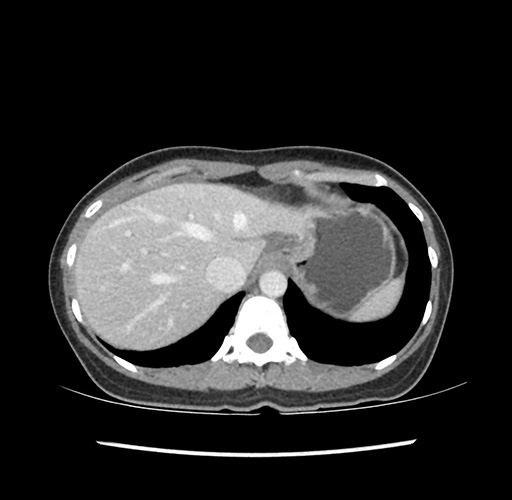

Imaging Analysis

Look through the patient's CT scan to identify any areas of concern for the necessary procedure.

Based on your CT findings, which issue(s) would give reason for "planned slowing down moment(s)" in this case?